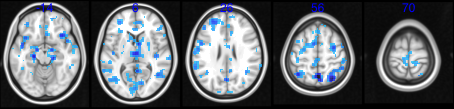

We conduct a comparative study between the HINT and three existing TC-GICA methods using synthetic data to illustrate its performance in detecting network differences and estimating spatial maps. Following Shi and Guo, (2016), we generated synthetic fMRI datasets from three underlying source signals (q=3)q=3) and considered various sample sizes with N=25,50,100𝑁2550100N=25,50,100 and 200200200. For each source or IC, we first generated 3D population-level spatial maps, i.e. s0(v)subscript𝑠0𝑣{s_{0}(v)}, with dimension 53×63×35363353\times 63\times 3 based on three selected slices from real fMRI imaging data. We then generated two covariates for each subject with one (xi1subscript𝑥𝑖1x_{i1}) being a categorical covariate simulated from Bernoulli(0.5)0.5(0.5) distribution and the other (xi2subscript𝑥𝑖2x_{i2}) being a continuous covariate randomly generated from a uniform (0,1)01(0,1) distribution. The strengths, 𝜷(v)𝜷𝑣\bm{\beta}(v), for these voxels were taken from {2.0,3.0,4.0}2.03.04.0\{2.0,3.0,4.0\}. In this paper, we generated synthetic data from more complex settings where the spatial sources and covariate effects can be overlapping. Specifically, we considered all four possible scenarios with the combinations of overlapping or non-overlapping source signals and overlapping or non-overlapping covariate effects. Figure 3 shows the activated regions in each IC and the covariate effect maps for the non-overlapping case. Highlighted regions correspond to active voxels. A full view of all combinations of overlapping and non-overlapping maps can be found in Table 4 of Appendix 3.

Refer to caption

Figure 3: Spatial maps used for the simulation (non-overlapping S0subscript𝑆0S_{0} and non-overlapping covariate effects).